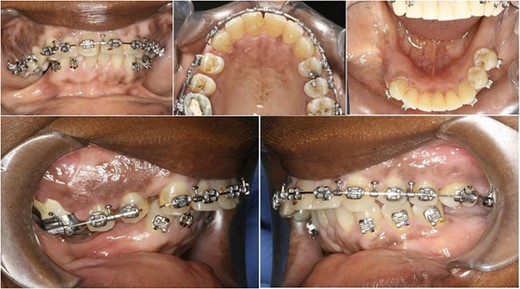

Preoperative orthopantomograph showing expansion of the right maxillary tuberosity.

The operation planned was a Le Fort I osteotomy with a right posterior segment osteotomy, which would set back the upper incisors by 6 mm, impact the upper left second molar by 4 mm and impact the posterior segment from the upper right first premolar (by 5 mm) to the upper right first molar (by 12 mm). No forward movement of the maxilla was planned. The segmental osteotomy was performed following down fracture of the maxilla and the final occlusion was aligned to a full coverage occlusal splint. The right descending palatal artery was sacrificed.